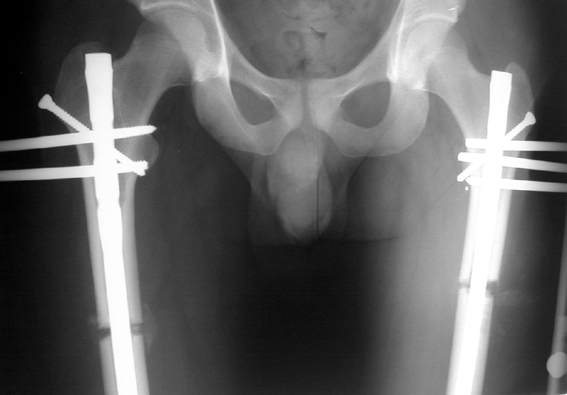

The application of the external fixator: Three Schanz screws are placed distally and three screws are placed proximally. At least 1 mm of distance shall remain between the screws and the nail.

In selected cases, we prefer to use a combination of a unilateral dynamic axial fixator and an interlocked intramedullary nail, in order to protect the length and alignment after the completion of the lengthening procedure. As a prerequisite for this technique, the narowest diameter of the medullary cavity shall be wider than 7 mm and the length of the nail segment distal to the osteotomy site shall be at least 8 cm. after the completion of the lengthening procedure.The intramedullary nail neutralizes shear and bending forces on femur during lengthening, shortens external fixation time, and protects newly formed bone against fractures. In our series, subtrochanteric osteotomy was performed in one case. No varus angulation occured despite the intramedullary nail.

Ilizarov stressed the significance of endosteal blood circulation for distraction osteogenesis. Although we placed the intramedullary nail after reaming the femur in all cases, the time for callus formation was not longer than expected. Thus we found that there is no slowing in the rate of new bone formation due to disruption of medullary blood flow. The rationale of this finding is revascularization that occurs following reaming of the medullary cavity, the fixation stability with the intramedullary nail and early functional weight bearing. The potential disadvantages of a combined use of external and internal fixation metods are increased blood loss, intramedullary infection, risk of fat embolism and excessive metal load.The most fearsome complication is a deep intramedullary infection (panosteomyelitis) triggered by pin tract infection.No such complication was encountered in our series. In order to avoid this complication, after the completion of lengthening the nail shaill be interlocked from the medial side, and contact of internal and external fixator pins shall be avoided.